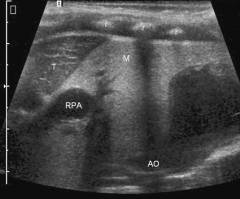

Неспецифический аортоартериит (болезнь Такаясу)

Неспецифический аортоартериит – хроническое заболевание, при котором развивается воспалительный процесс в аорте и отходящих от нее крупных сосудов. Реже поражение при заболевании может захватывать легочные артерии.

Заболевание, как и другие системные васкулиты, встречается редко. Женщины болеют в 3 – 8 раз чаще мужчин.

Проявления болезни Такаясу

Патологические изменения в сосудах при неспецифическом аортоартериите протекают в две стадии:

- В начале под действием иммунных клеток на внутренней стенке сосуда появляются специфические разрастания – гранулемы.

- В дальнейшем воспалительный процесс сменяется рубцеванием, происходит склероз сосудов.

| Повышение артериального давления | Возникают симптомы, характерные для артериальной гипертонии. При поражении брюшной части аорты и отходящих от нее почечных сосудов нарушается поступление крови и кислорода в почки. Запускаются патологические механизмы, приводящие к повышению уровня артериального давления.

Если поражена дуга аорты и сосуды, отходящие к верхним конечностям, то отмечаются различающиеся показатели артериального давления на правой и левой руке. |

Диагностика неспецифического аортоартериита